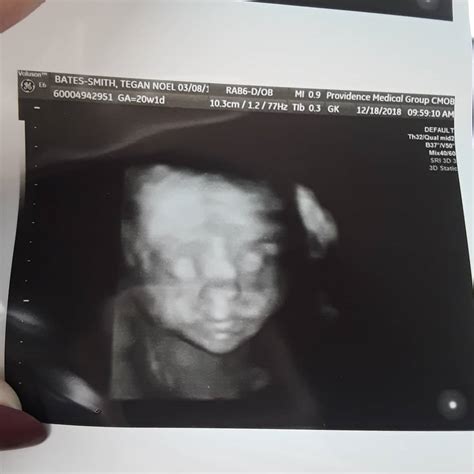

Reaching the midpoint of your pregnancy is a monumental milestone that brings a mix of excitement, nerves, and anticipation. Among the many prenatal appointments on your calendar, the anatomical scan at 20 weeks stands out as one of the most critical. Often referred to as the "mid-pregnancy ultrasound" or the "anomaly scan," this diagnostic procedure provides a comprehensive look at your developing baby’s physical structure and overall health. It is a moment where the abstract feeling of pregnancy becomes startlingly real as you get to see your baby's features, movements, and heartbeat in vivid detail on the screen.

The anatomical scan at 20 weeks is a detailed medical ultrasound performed by a trained sonographer or radiologist. Unlike earlier ultrasounds that may have focused on confirming the pregnancy or dating the gestation, this scan is designed to evaluate every major organ system and physical feature of the fetus. It typically takes between 30 to 60 minutes, depending on the baby's position and how cooperative they are during the process.

Beyond the Medical Data

While the clinical aspect of the anatomical scan at 20 weeks is the priority, many parents cherish this experience as a bonding moment. You may be able to see your baby sucking their thumb, yawning, or kicking. Some facilities provide photos or digital files of these images. Remember to discuss your expectations with your partner and your healthcare provider beforehand regarding how you wish to handle the revelation of the baby's sex or other findings.